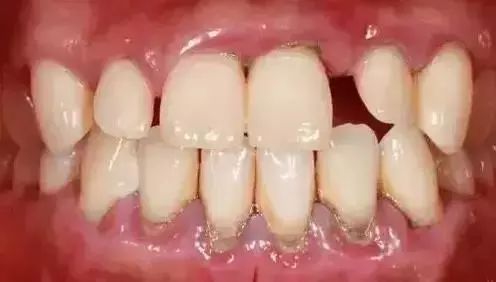

因为你看不见的地方是这样的↓↓↓

如果更严重点,有可能是这样的↓↓↓

牙龈周边积聚着大量黑褐色牙结石并伴有口腔异味,牙龈红肿明显,时间一长,很有可能造成牙齿松动脱落。